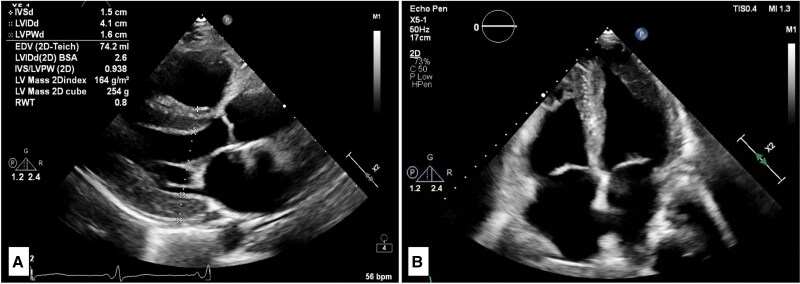

Case summary: A 56-year-old female with a longstanding history of systemic lupus erythematosus presented with progressive dyspnoea, fatigue, and fluid overload. Initial investigation revealed LVH with restrictive physiology, elevated cardiac biomarkers, and non-specific findings on echocardiography suggestive of an infiltrative cardiomyopathy. The diagnosis remained uncertain until an endomyocardial biopsy (EMB) confirmed HCQ-CM, characterized by the presence of curvilinear inclusion bodies. Following cessation of HCQ, there was a significant clinical improvement, with the patient achieving NYHA class I status at 6 months follow-up.